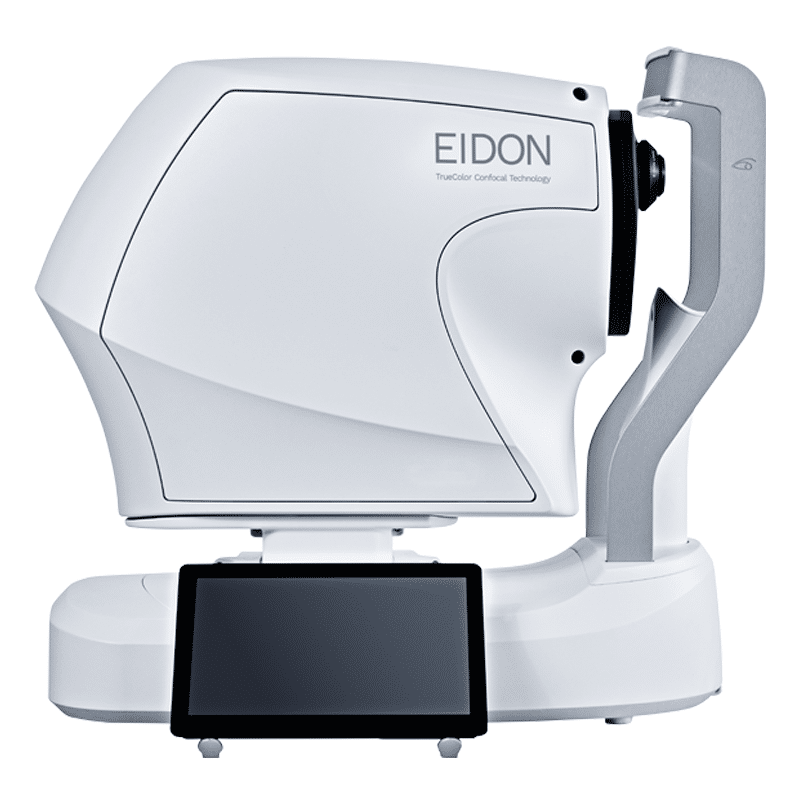

The EIDON AF is also available without auto fluorescence (EIDON) and with fluorescein angiography (EIDON FA). Contact us for more information regarding any model.